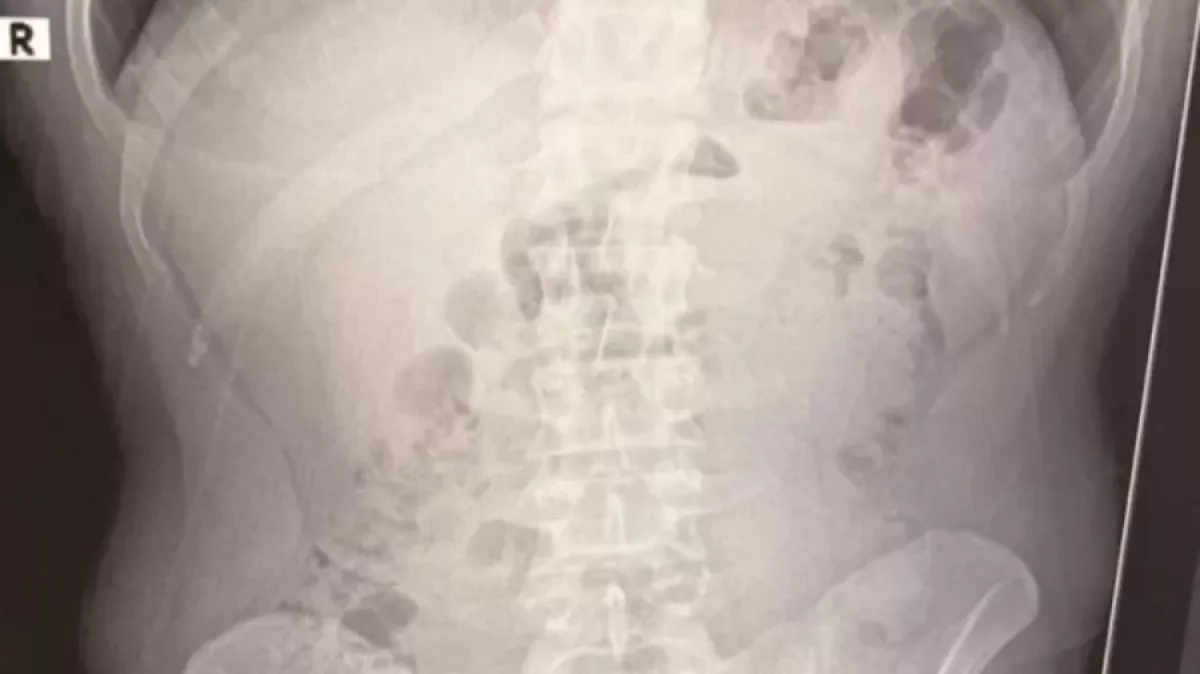

По результатам рентгеновского обследования было выявлено наличие капсул с метамфетамином в их желудках. Суд принял решение о содержании иранских граждан под стражей.